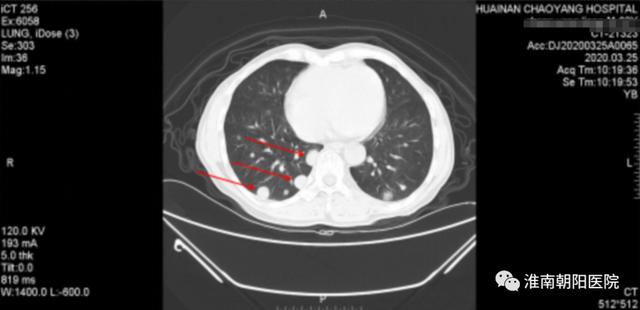

(红色箭头提示肺内的病灶明显增大了)

近年来,淮南朝阳医院肿瘤中心努力学习先进医疗技术,经过仔细会诊讨论,为张大爷制定了「免疫治疗+分子靶向治疗+化疗」三种联合综合治疗方案。3 月 26 日「阿帕替尼+卡瑞利珠单抗+卡培他滨」三种药物联合治疗开始。经过 3 个多月 4 疗程的治疗,张大爷身体状况好转,进食不畅、恶心、纳差的症状基本上都消失了,体重也增加了 10 斤。

7 月初我们复查时惊喜地发现两肺多发转移灶和右侧胸廓入口处淋巴结明显缩小。

上图是张大爷免疫综合治疗后的 CT,可以看见以前的转移灶基本消失了